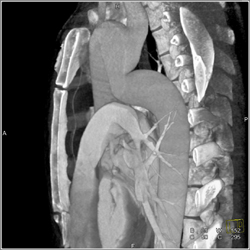

Diagnosis

Stent in RCA